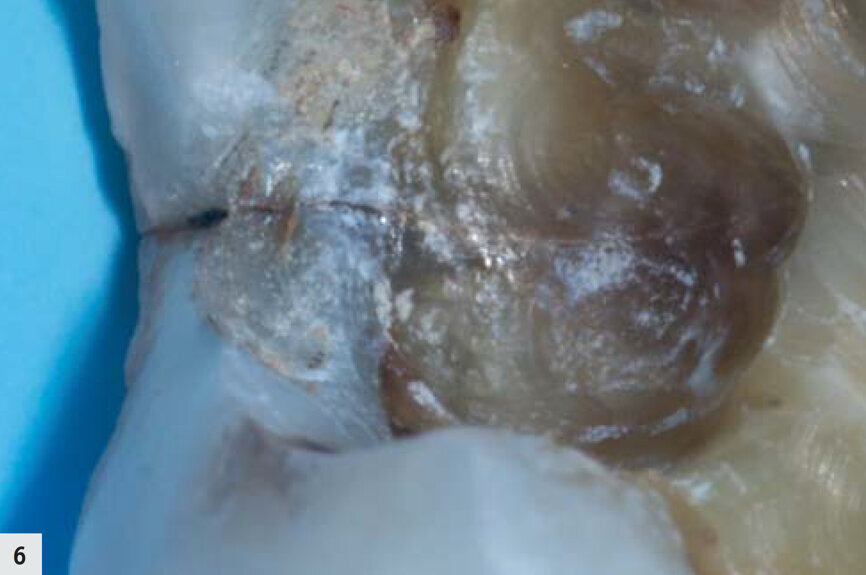

Figs. 6–7 : Fissure dans la boîte proximale, devenue plus apparente après l’élimination de la boue dentinaire.

Une autre dent présentait une profonde fissure au niveau de la limite proximale (Fig. 6). Après le nettoyage (Fig. 7), la structure était mieux visible grâce à la lampe D-Light Pro en mode détection. La structure des tissus dentaires est devenue plus apparente, la dentine émettant davantage de fluorescence dans une couleur verte bien distincte. À ce moment, on pouvait clairement observer la propagation de la fissure dans les couches plus profondes de l’émail, ainsi que dans la dentine (Fig. 8). La fissure a été mieux nettoyée puis préparée à l’aide du dispositif AquaCare Twin (Velopex) chargé avec une fine poudre de coupe d’oxyde d’aluminium, sous pression d’air et refroidissement par eau (Fig. 9). En mode détection, il est possible de confirmer en un coup d’oeil que les limites marginales de la préparation sont toutes positionnées dans l’émail sain (Fig. 10). La fissure extrêmement fine que l’on peut observer est superficielle et limitée à l’émail.